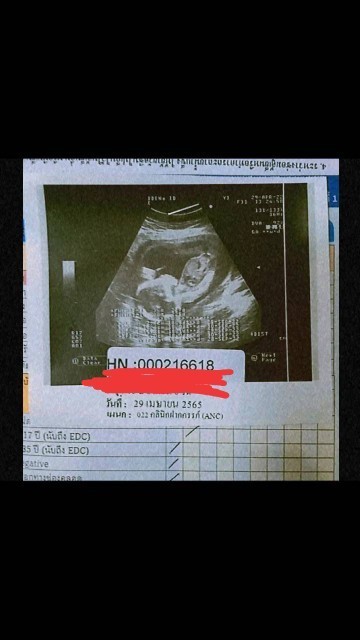

ภาพ ซาวตอน5เดือน มีใครเหมือนบ้านนี้มั้ยคะ ในถาพน้องจะท้องใหญ่ แต่คุณหมอไม่ได้แต้งอะไรค่ะ เป็นปกติมั้ยคะ มีอม่ๆคนไหนเป็นเหมือนกันบ้างคะ

13วีคค่ะน้องตัวใหญ่ปกติดีค่ะแม่

12 สัปดาห์ค่ะ